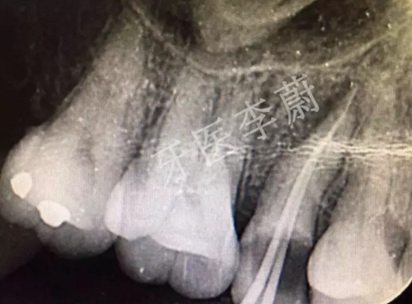

15牙根管預(yù)備試尖片

15牙根管充填術(shù)后X牙片